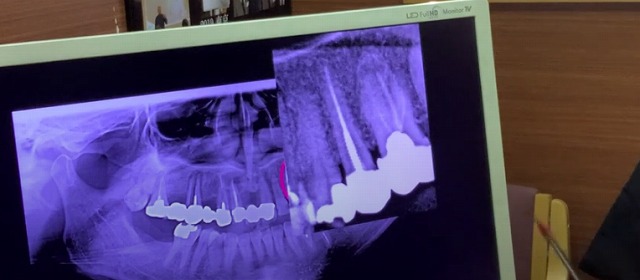

そして

ばい菌が侵入したり

歯を支えている骨が溶けたりすると

歯の根っこの周囲が黒く溶けてきたりして

レントゲンでは黒く写ってきます。

ですから

その歯の周囲には硬い骨がない

つまり骨がない

歯の根っこが割れているのでばい菌が入って

骨が溶けたのではないかと

推測することができるということになります。

歯の神経が生きているのか?死んでいるのか?と推測し判断するのは

こうやってやっています。